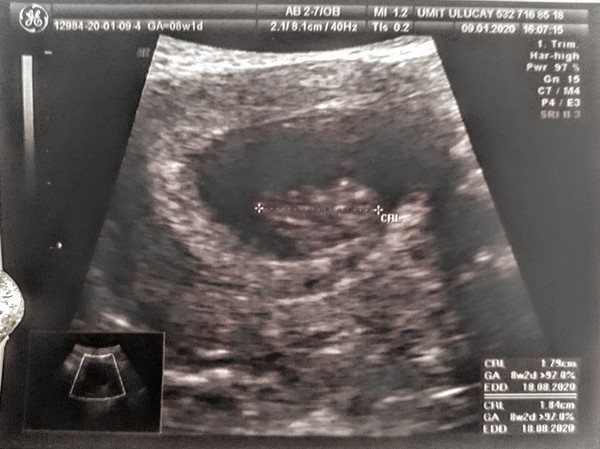

sel2223 · 09/01/2020 16:10

Just back from an early scan at 8+2

Not the best picture but it was great to see our jelly bean and hear their heartbeat 😊

@PandaPink thank you. I'm pleased everything went well with your reassurance scan today!

@LoloFuentes Yes. We're in Turkey and the private clinic here scanned to confirm the pregnancy at the very beginning then they do a follow up for free.

@LoloFuentes I know, it's such a long wait to the 12 week scan. The first trimester is really dragging and I've been so anxious this last week for some reason so this scan was very welcome.

I know it's early days and anything can happen but it was so reassuring to hear the heart beat (175bpm - which I was told is very strong for 8 weeks)